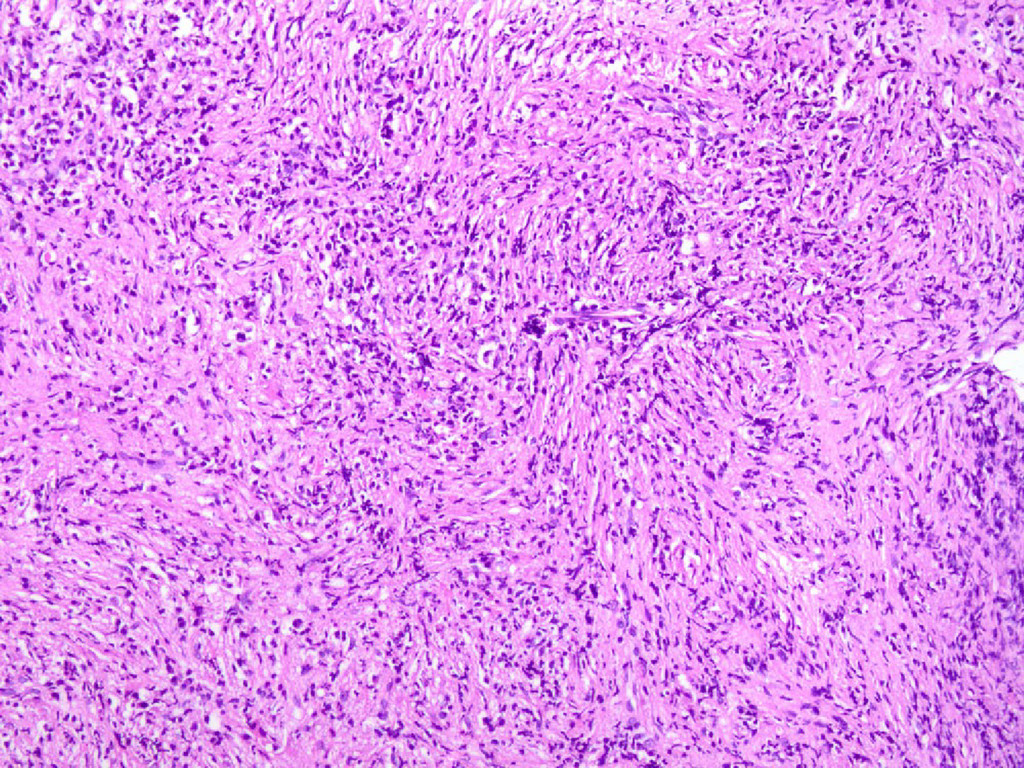

1. Male 68 years. Right nasal block. CT: Expansile soft tissue

mass posterior aspect of right maxillary sinus. Destruction of postero- medial wall of sinus with soft tissue bulging into the nasal cavity. CASE 1

3. 45 year old woman. h/o watering of the Left eye

and protrusion of left eyeball 4 years. HRCT Orbit: Enhncing soft tissue density lesion in the infromedial aspect of Left orbit with involvement of Left inferior rectus muscle, extension into nasal cavity, ethmoid air cell and maxillary sinus. Biopsy from the nose CASE 10